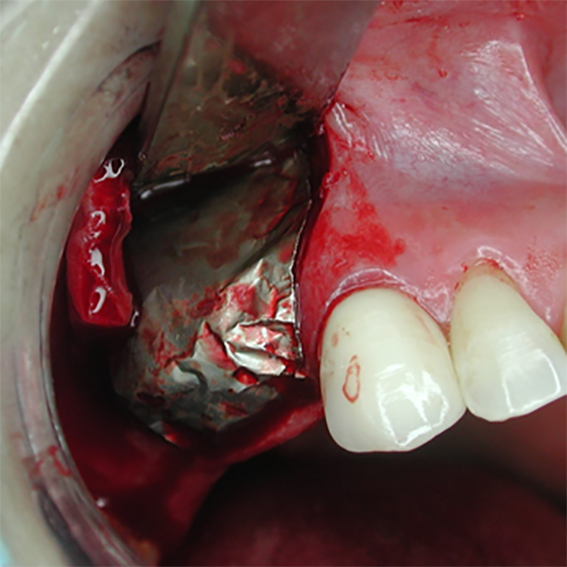

- Very pliable and mouldable with good adaptation

- No need for pin/screw fixation – immobilized by replaced soft tissue flap

- Excellent would healing underneath

Pure titanium membrane of ultra-thin thickness of about 10 microns (0.01mm). Totally inert, biocompatible and non-biological thus removing the fear of disease transmission from collagen of bovine source. It allows ease of handling and adaptation over the operative site. Because of its mouldability, it does not require pin or screw fixation, thus avoiding the risks of pin or screw swallowing or aspiration. Excellent clinical performance in guided tissue regeneration. Resistance to infection after exposure. Primary wound closure is not necessary. No tissue reaction or wound infection.